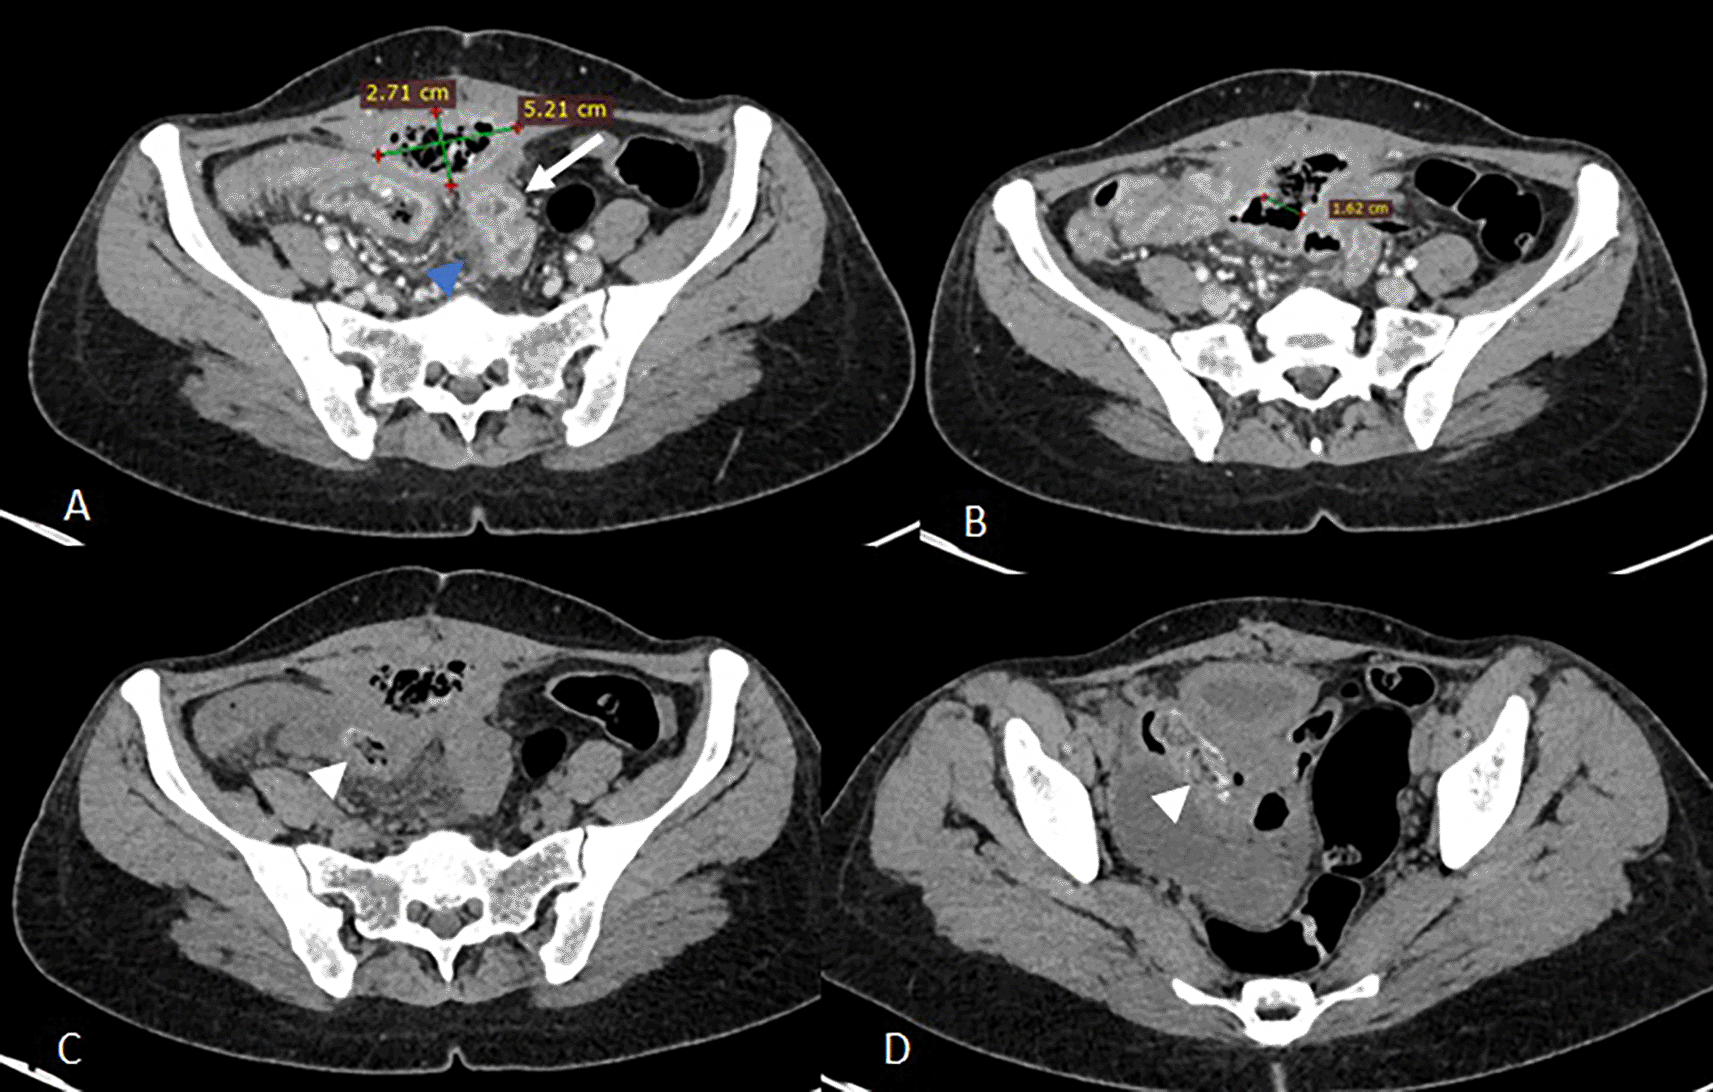

Abdominal computed tomography (CT) demonstrated a 9 × 8 × 5 cm pelvic-abdominal mass, anterior to the bladder and abutting the anterior abdominal wall. The lesion contained heterogeneous fluid and air with peripheral contrast enhancement, associated with agglutinated intestinal loops and multiple enlarged locoregional lymph nodes (Figure 1). There was concern for enteric fistula and communication with the urinary bladder.

Images C and D show two intraluminal foreign bodies in the ileal loops, spontaneously dense and heterogeneous, forming air bubbles (white arrowheads).